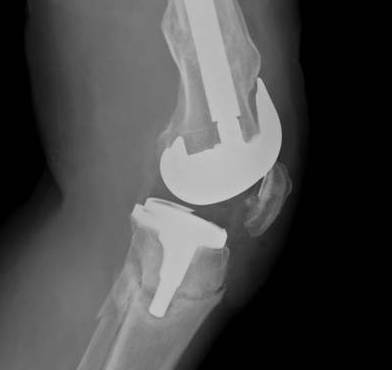

2.  Retrograde IM Nail

TKR Periprosthetic FractureTKR Periprosthetic Fracture 2TKR Periprosthetic Fracture Retrograde Nail 1TKR Periprosthetic Fracture Retrograde Nail 2

Issue

May be biomechanically superior

Have to open TKR to perform operation

- risk deep infection

Indications

Technically feasible

- CR knees contra-indicated

- must have sufficient sized hole in PS femoral component

- consult company as to suitablity

- small diameter nail